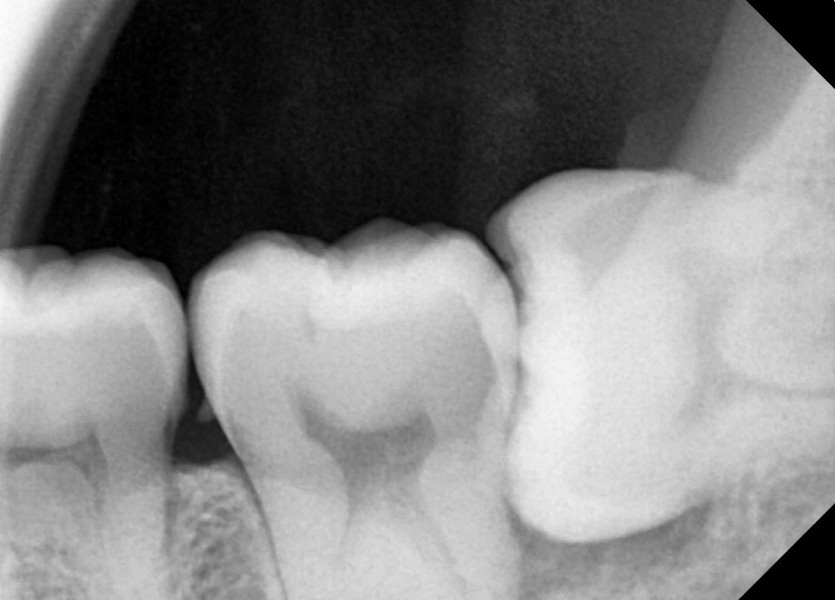

#38,48 사랑니 발치

구강 외과 전문의가 당일 발치했습니다.